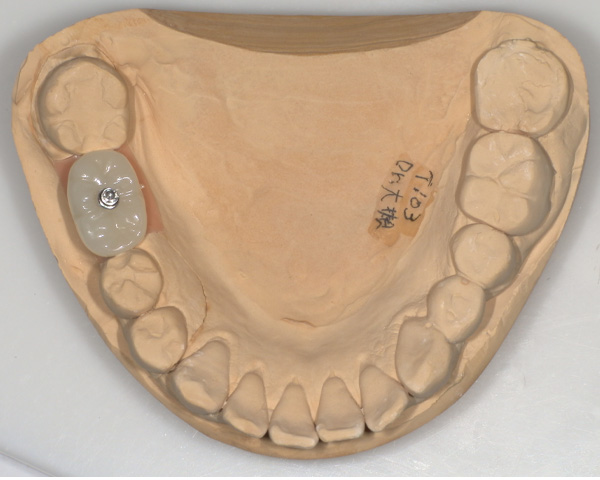

インプラント手術から3ヵ月後、型どりをして、仮歯を製作しました。

レントゲン画像 -